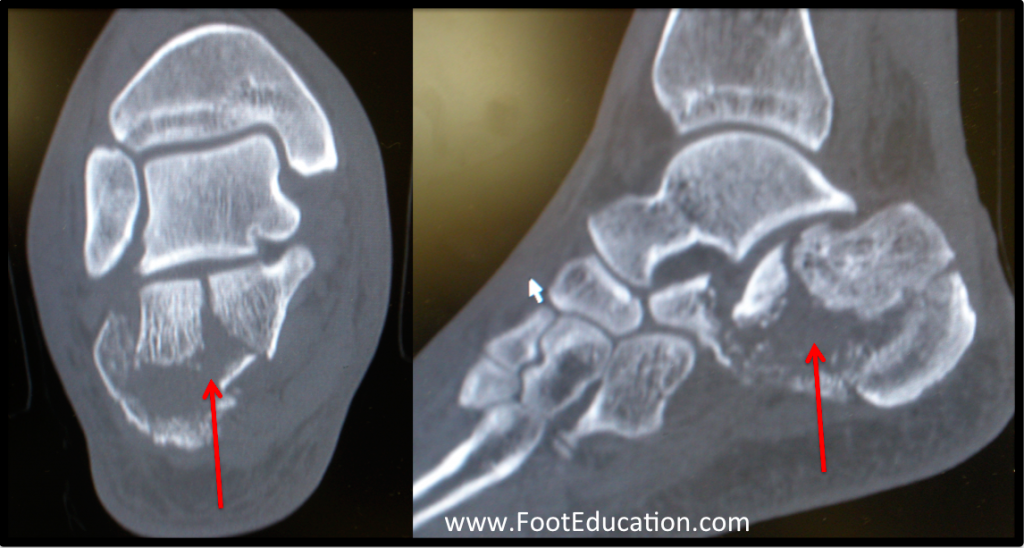

Calcaneal Fractures FootEducation Classification De Sanders Calcaneum Sanders type ii and iii posterior facet displacement >2 to 3 mm, flattening of bohler angle, or varus malalignment of the tuberosity anterior process fracture with >25%. The sanders classification system is specific for intraarticular calcaneal. Use coronal image with the widest undersurface of the posterior facet of the talus. Sanders classification of intraarticular fractures of the calcaneus. Sanders classification. Classification De Sanders Calcaneum.